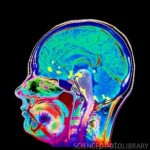

מחלת האלצהיימר תוקפת אחד מכל חמישה אנשים. הדרך לאבחן את המחלה ולהבדיל אותה ממחלות דמנציה אחרות איננה פשוטה- כיום הנוירולוגים מאבחנים אותה על-ידי מבחני הגיון וזיכרון ודיווחים על הסתגרות חברתית. בעשור האחרון פותחו סריקות מוח של PET (פליטת פוזיטרונים), כשהפיתוח האחרון משתמש בחומר צבע רדיואקטיבי בשם “אמיוויד”.  חומר זה מתרכז ברבדי  העמילואיד,  החומר החלבוני המצטבר… המשך הקריאה